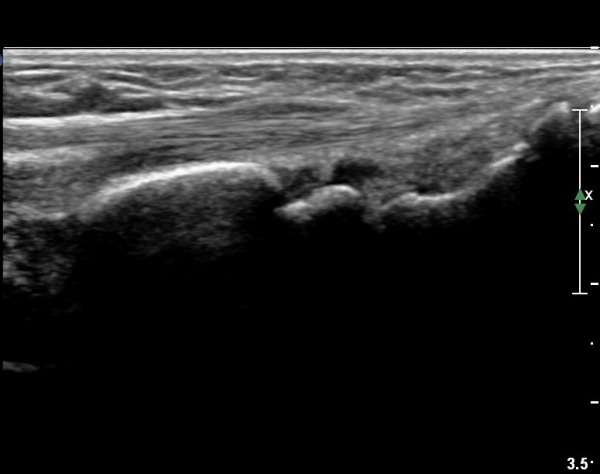

ŽÃËÀÚ¸¦¾à°£ ¿äÃøÀ¸·Î À̵¿ÇÏ¿© Àå¿äÃø¼ö±Ù½Å°Ç Á¾´Ü¸é°Ë»ç¿¡¼­ Àå¿äÃø¼ö±Ù½Å°ÇÀÇ

ºÎÁ¾ÀÌ °üÂûµÇ°í ½ÅÀü°Ç Ç¥Ãþ¿¡¼­ À幫Áö½ÅÀü°ÇÀÌ °üÂûµÈ´Ù(»çÁø 2).